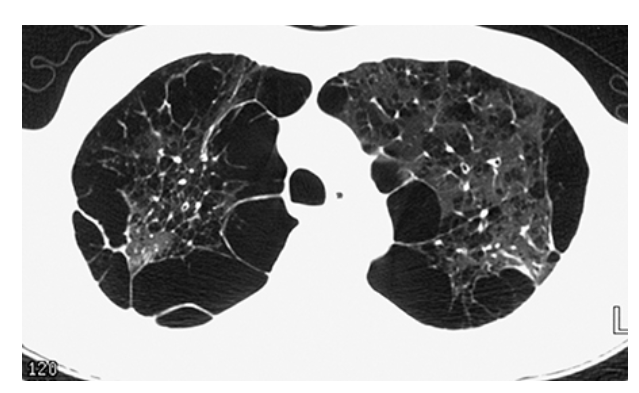

Pulmonary Fibrosis. HRCT of the chest shows honeycombing in the peripheral lung bases with associated traction bronchiectasis.